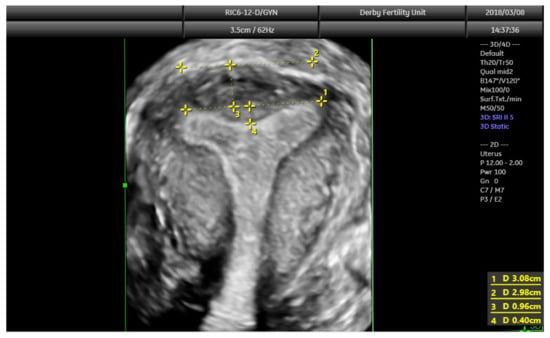

The diagnostic accuracy of 3D ultrasound compared with laparoscopy ± hysteroscopy in diagnosing CUA is highest among other imaging modalities including MRI. The diagnostic accuracy of 3D ultrasound is reported as 97.6% with sensitivity and specificity of 98.3% and 99.4%, respectively [18]. The morphology of the uterus is best examined in the coronal plane (Figure 8) using the interstitial portions of the fallopian tubes as reference points. A line joining the tubal ostia (interostial line) is the reference line (Figure 9). A parallel line on top of the fundus can be drawn and the vertical distance between this line and the interostial line is the uterine wall thickness. In cases of septate uterus, a parallel line along the apex of the internal midline indentation is drawn and its vertical distance from the interostial line is the septal length. The vertical distance between the parallel line along the bottom (apex) of the external indentation and interostial line is the depth of the external cleft in cases of partial bicorporeal (bicornuate) uterus.

The classification utilising 3D ultrasound based on the publication by Salim et al. (2003) is described in Table 2 [14]. The ESHRE/ESGE classification of uterine anomalies based on the 3D scan assessment is based on using uterine wall thickness as the reference. An internal indentation at the fundal midline of more than 50% of the uterine wall thickness is used to diagnose a septate uterus. On the other hand, a bicorporeal (bicornuate) uterus is diagnosed when the external indentation is more than 50% of the uterine wall thickness. The ASRM in the publication ‘Uterine septum: a guideline’ has suggested diagnosis of normal or arcuate uterus when the distance between the interostial line to the apex of indentation is less than 1 cm and the angle of indentation is more than 90° [19]. It also reported an arcuate uterus as a normal variant and clinically irrelevant. A septate uterus is diagnosed when the indentation depth is more than 1.5 cm and the angle of indentation less than 90°. A bicornuate uterus is diagnosed when the external fundal indentation is more than 1 cm.

Figure 9. 3D coronal plane of uterus with assessments: interostial line (measurement 1); a parallel line along the serosal surface (measurement 2); uterine wall thickness (measurement 3) and septal indentation length. This uterus is not septate, but may be classified as arcuate uterus, which has no clinical relevance based on the recent ESHRE and ASRM guidelines.